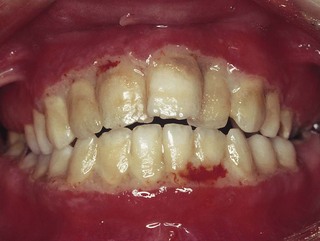

All the features of the established lesion are present in addition to the following:

gross gingival inflammation, fibrosis and some shrinkage (Fig. 33.4)

bleeding pockets of more than 3 mm

tooth mobility and migration

irregular alveolar bone loss around the teeth

gingival recession

halitosis and offensive taste

usually little or no pain

may or may not be associated with systemic disease.

image

Fig. 33.4 Gross periodontal disease. Note the highly inflamed gingivae and calculus deposits.